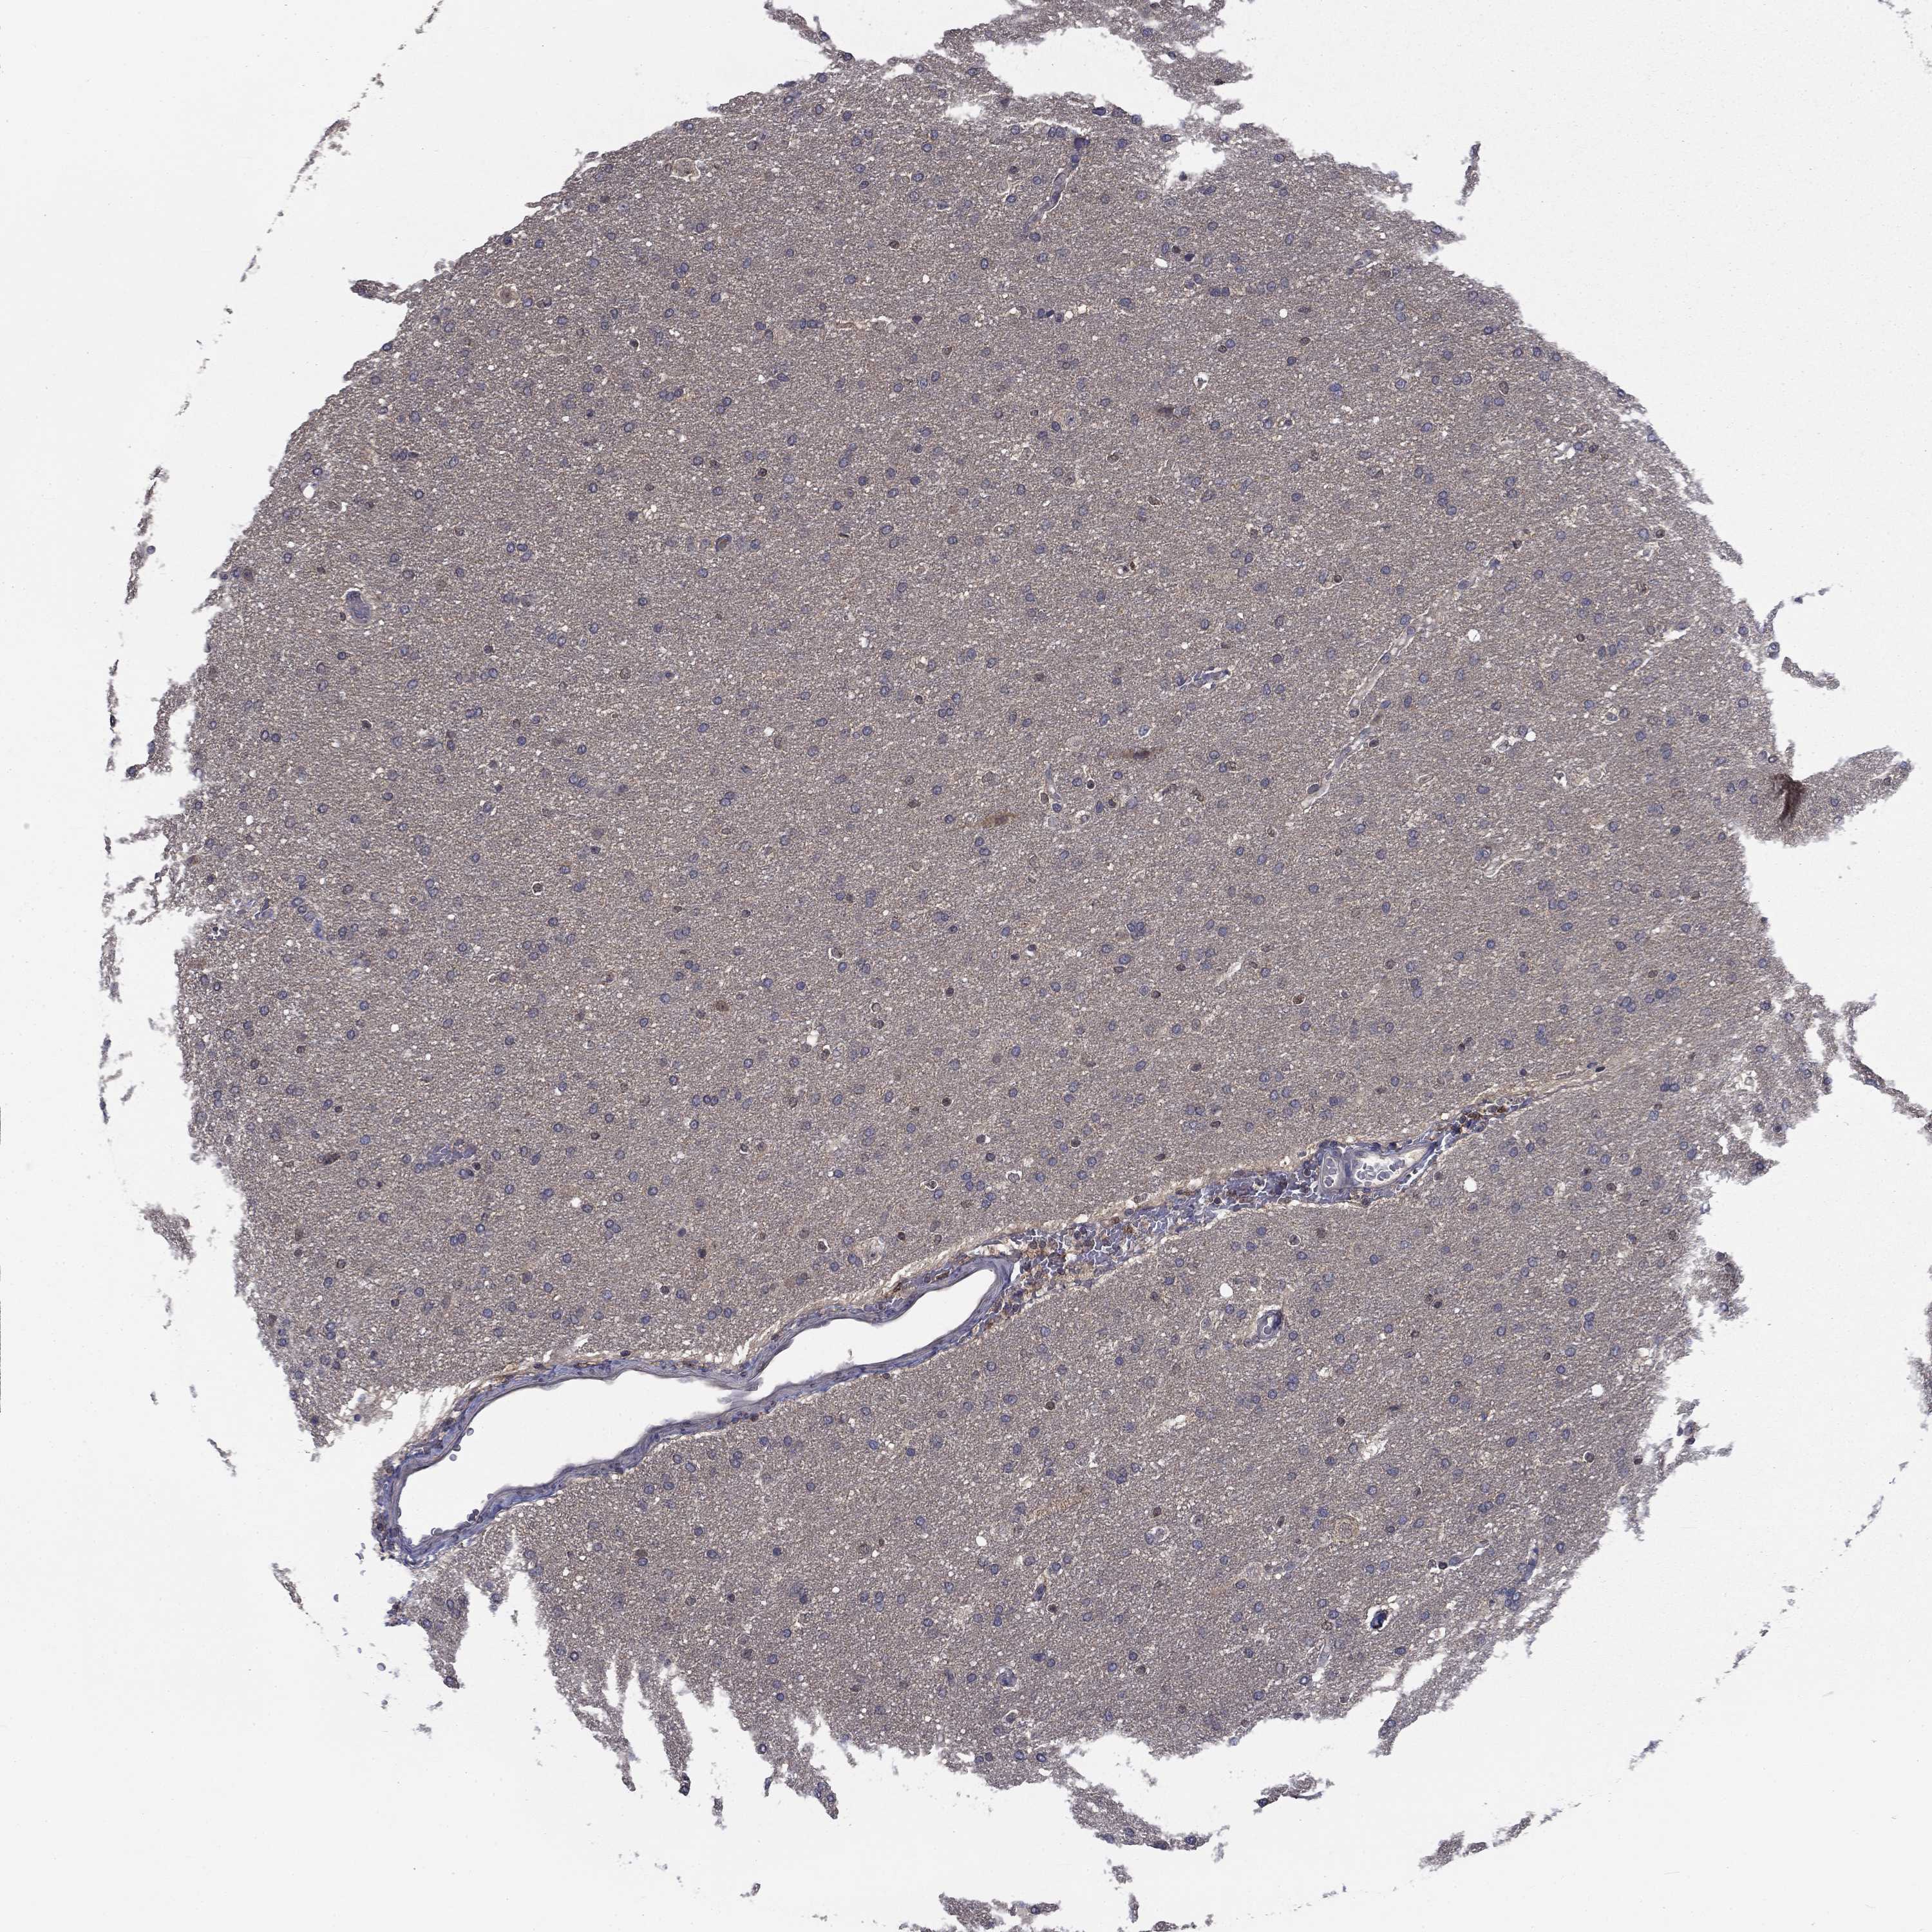

GLIOMA - Protein expressioni

A mouse-over function shows sample information and annotation data. Click on an image to view it in a full screen mode. Samples can be filtered based on level of antibody staining by selecting one or several of the following categories: high, medium, low and not detected. The assay and annotation is described here.

Note that samples used for immunohistochemistry by the Human Protein Atlas do not correspond to samples in the TCGA dataset.

Antibody stainingi

Antibody staining in the annotated cell types in the current human tissue is reported as not detected, low, medium, or high, based on conventional immunohistochemistry profiling in selected tissues. This score is based on the combination of the staining intensity and fraction of stained cells.

Each image is clickable and will lead to virtual microscopy that enables deeper exploration of all samples and also displays staining intensity scores, fraction scores and subcellular localization as well as patient and tissue information for each sample.

Antibody HPA036999

Antibody HPA041289

Staining

High

Medium

Low

Not detected

Intensity

Strong

Moderate

Weak

Negative

Quantity

>75%

75%-25%

<25%

None

Location

Nuclear

Cytoplasmic/membranous

Cytoplasmic/membranous,nuclear

Glioma, malignant, High grade

Glioma, malignant, Low grade